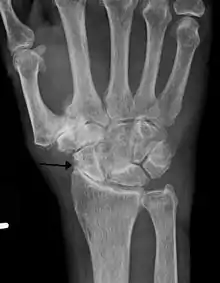

Severe osteoarthritis and osteopenia of the carpal joint and 1st carpometacarpal joint